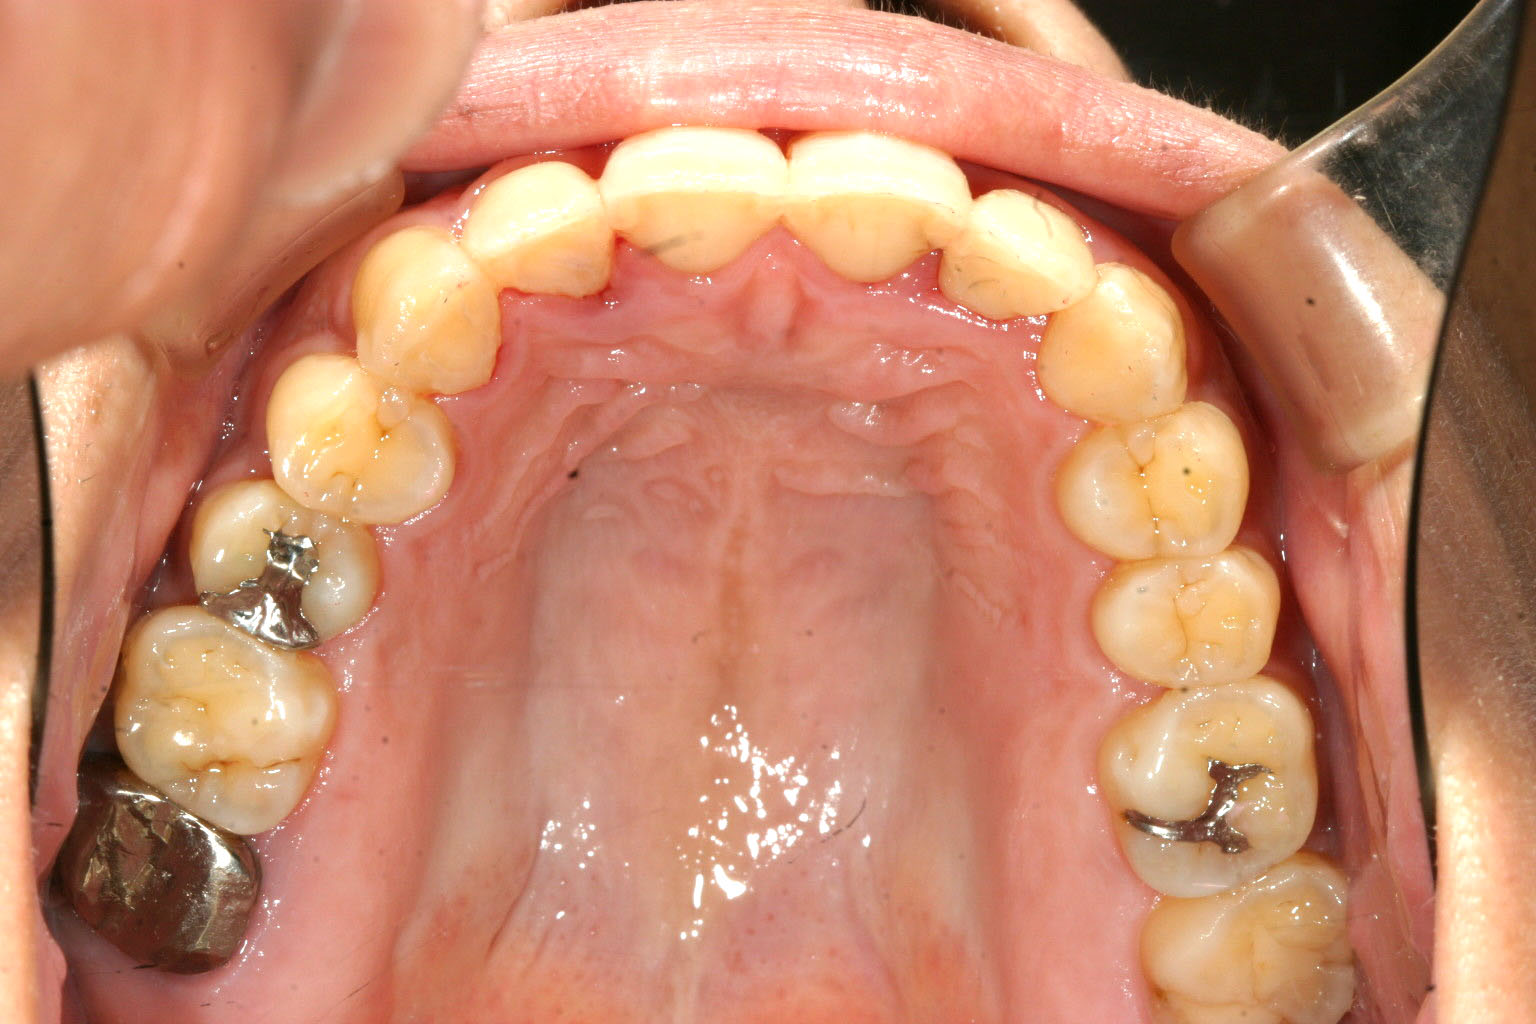

アーチが狭いお陰で前歯が前突しています。

下顎にも少し叢生が見られます。